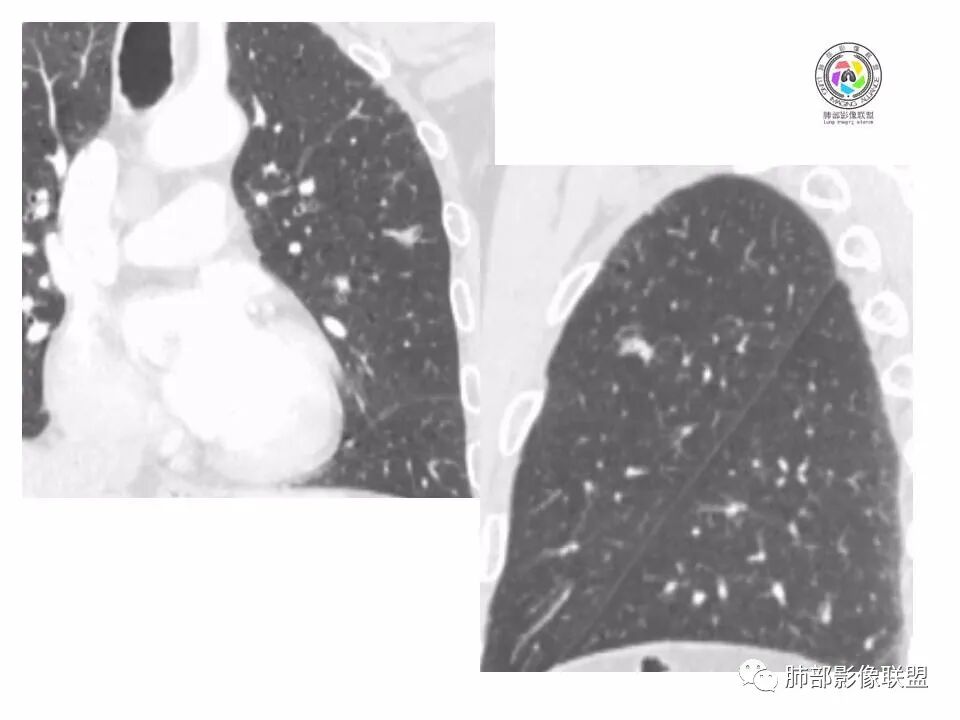

左肺上叶小结节,边缘毛糙,血管集束,支气管截断,强化较明显,但U型凹陷,部分边缘平直,总体感觉恶性大于良性,首选腺癌,鉴别炎性肉芽肿。

左上肺结节,月牙征,边缘纠集有收缩力,小空泡,血管增粗进入,纵隔淋巴结增大,考虑恶性,隐球菌待排。

老年男性,左上肺结节,边缘毛糙,临近血管进入增粗,内部隐约可见小空泡或远端扩张支气管,血管集束并伴月牙铲,有个横断界面看似像脐凹征,常规考虑腺癌,鉴别隐球。

结节,分叶,边缘毛糙,小空泡,血管集束并伴月牙铲,有强化,老年男性,考虑腺癌,建议复查除外结核。

左肺上叶混合密度结节,边缘见边缘清楚磨玻璃,分叶,U型凹陷,首先考虑腺癌。

左肺上叶结节影,边缘可见分叶,血管集束及月牙铲征,病灶内见小空泡影,考虑腺癌可能。

结节密度不均匀,混合磨玻璃结节,大部分实性部分,边缘清,月牙铲征,肿瘤微血管征,考虑肺癌。

老年男性,体检发现左肺上叶结节,周围浅分叶伴磨玻璃影,有血管相连,U型凹陷,纵隔见肿大淋巴结,考虑为恶性,腺癌可能。

左肺形态不规则结节,边缘收缩,毛刺,有月牙铲,纵隔窗比肺窗小,不密实,近段血管与病灶相连,强化不明显,老年男性,综合考虑,恶性,腺癌,鉴别炎性结节。建议穿刺。

老年男性,左肺上叶结节,边界清,不规则,有毛刺,血管集束,空泡,边缘有气肿带,考虑腺癌,鉴别肉芽肿。

左肺上叶小结节,边缘毛糙,血管集束,支气管截断,有月牙铲,首选腺癌,鉴别炎性肉芽肿。

左上肺实性小结节,短毛刺,月牙铲,似见小空泡,血管集束,有轻度强化,首先考虑腺癌。

老年男性,肺气肿背景,左肺上叶小结节,大部分边缘平直,部分边缘膨隆,局部可见月牙铲,边缘少许磨玻璃,边界清晰,血管进入,轻度强化,首先考虑腺癌,常规抗炎后复查,除外炎性结节。

左上肺结节,短毛刺,空泡,月牙铲,脐凹征,考虑腺癌。

左肺上叶混合密度结节,边界清,分叶,毛刺,血管进入,月牙铲,有强化,首先考虑腺癌,有平直边,收缩力不明显,常规先抗炎。

左上肺结节分叶,边缘毛糙,小空泡可能,血管集束,月牙,纵隔窗面积小于肺窗,有磨玻璃成份,有强化,老年男性,白细胞高,恶性的征象都有,但磨玻璃的形态和边界不好评估,实性为主,看形态和边缘局部较散缺乏饱满感,顶着压力反着来猜炎性可能大。复查不消失会考虑腺癌或黏液腺癌。

老年男性,肺气肿背景,左肺上叶实性结节,边界清,边缘平直为主,细长毛刺,较明显强化,考虑炎性病灶,隐球?

老年男性,左肺上叶结节,边缘可见长毛刺、较软,并可见分叶,周围可见清楚磨玻璃密度,内可见空泡征,增强后呈均匀强化,良恶性征象都有,感觉收缩力不强,化验白细胞偏高,建议抗炎治疗后复查除外腺癌。

老年男性,左肺上叶混合密度结节,空泡,分叶,血管集束,有强化,考虑腺癌;细长软毛刺,血管走行自然,边缘有平直收缩,白细胞高,肿标正常,考虑炎性结节。猜炎性结节,鉴别腺癌。

左肺上叶前段mGGN,边缘见毛刺及月牙铲,考虑腺癌,需要薄层图像确认所见征象。

左肺上叶结节,分叶,边缘毛糙,小空泡,月牙铲,有强化,考虑浸润性腺癌,鉴别炎性肉芽肿。

患者老年男性,体检发现。查癌胚抗原不高。血常规血象升高。胸部CT:肺气肿背景,左肺上叶近胸膜下实性结节,边缘光滑,边界清楚,可见毛刺、血管集束、月牙铲征象,增强不明显,内可见低密度区,综合考虑恶性病变,腺癌可能大,鉴别结核及炎性结节。

老年男性,左肺上叶结节,周围浅分叶伴磨玻璃影,有血管相连,月牙铲。纵隔见肿大淋巴结,但白细胞高。腺癌首先,需排除炎性假瘤。抗炎治疗后复查。

老年男性,体检发现左肺结节,分叶、脐凹、月牙铲及月牙铲附近有边缘清楚的磨玻璃影,上述征像均指向恶性肿瘤,有疑问的地方:毛刺软无力,无胸膜牵拉及白细胞计数升高。整体是腺癌,需要抗议后复查以排除炎性病变。

图片有限,左肺上叶结节病灶,有张力,有收缩及小泡征,边缘可见月牙征,周围长毛刺及血管集束征,增强目测有中度以上强化,首先考虑恶性病变,腺癌。

左肺上叶前段小结节,边缘稍毛糙,月牙铲,血管进入可疑脐凹征,小空泡?增强有强化,老年男性,要高度警惕腺癌,但感觉毛刺偏细软,周围磨玻璃不明显,常规查隐球菌荚膜抗原除外隐球菌,血象高,抗炎后短期复查除外炎性结节。

左肺上叶mGGN,边缘收缩平直为主,肺窗显示清楚,纵隔窗体积缩小,未见胸膜牵拉,倾向感染性结节,隔期复查。